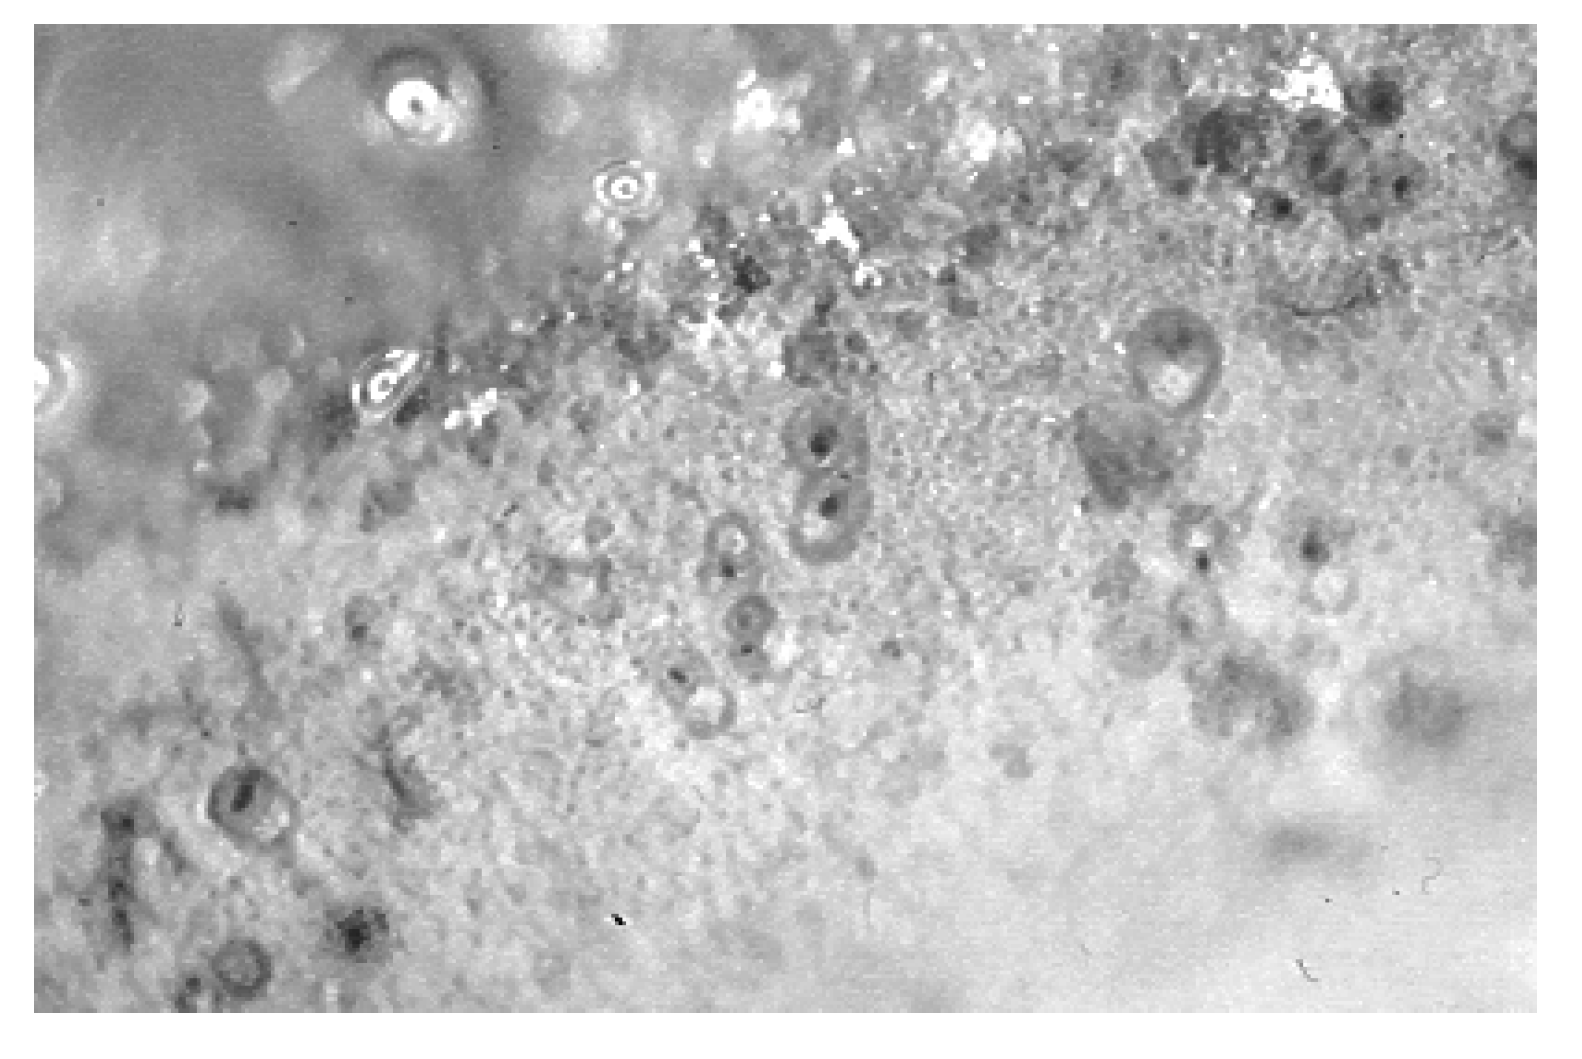

3.2.2. Direct Contact Tests

- −

- "A", alloys that reveal cytotoxicity close to Teflon (90% to 100% cell viability). In this group are silver-palladium-based alloys, gold-rich alloys, and medium-grade gold alloys.

- "B", alloys that reveal a cellular viability of between 70-89% and that do not represent any risk of toxicity in the oral environment. In this group are classified the titanium-based alloys and silver-based alloys.

- "C", alloys that reveal a cellular viability between 45 -69%, therefore represent significant cytotoxicity, and which may represent a risk of toxicity from their use in the mouth.

- "D", alloys that reveal a cell viability < 44%, therefore have a strong cytotoxic response. In this group are classified metals such as nickel, copper and gold-nickel and gold-cadmium alloys.